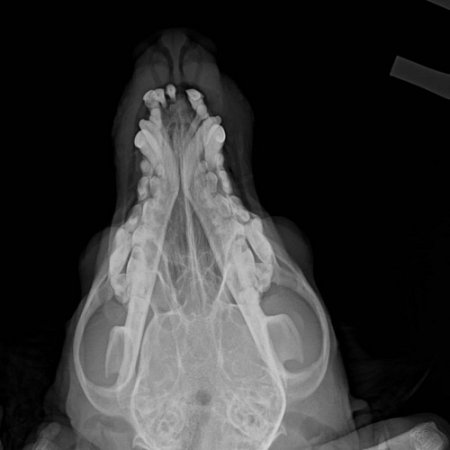

Охранники связались с Ольгой, которая занимается помощью животным, и раненую собаку отвезли в ветклинику. Визуальный осмотр и рентген показали множественные травмы челюсти, разрывы пасти, выбитые зубы. Если бы пес вцепился не в пасть, а в позвоночник, исход, вероятно, был бы смертельным.